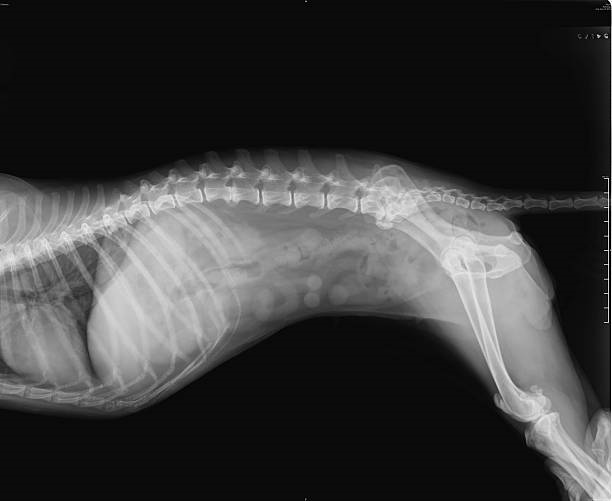

O raio x é uma ferramenta essencial para diagnósticos precisos em animais, pois permite visualizar estruturas internas e identificar alterações que podem passar despercebidas em exames clínicos.

O raio x é um exame não invasivo e indolor, que pode ser realizado de forma rápida e segura nos pets. Ele é fundamental para diagnosticar fraturas, identificar corpos estranhos no organismo, avaliar órgãos internos, detectar problemas pulmonares, entre outras aplicações.

Além disso, o raio x ajuda os veterinários a planejarem tratamentos precisos e eficazes para a saúde e o bem-estar dos animais.